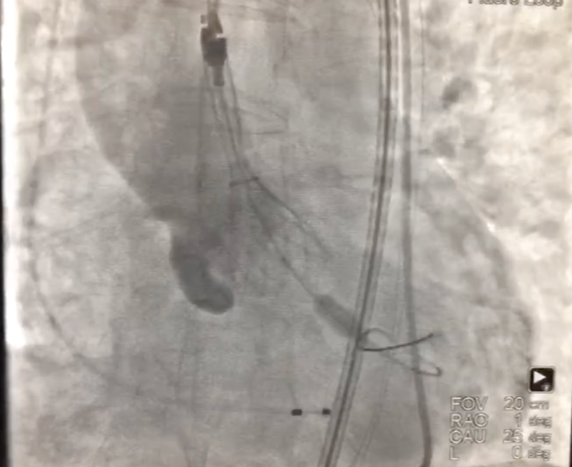

1、經右股動脈將Emboshield Nav6放栓塞裝置輸送至左、右頸內動脈。

2、經左股動脈入路,順利跨瓣后,選取20 mm球囊于180 bpm下快速起搏預擴,顯示無漏,左、右冠脈未受影響,但可見左冠竇、無冠竇巨大鈣化團塊。

3、按照既定策略,選擇24 mm VitaFlow微創瓣膜,于180 bpm快速起搏下,快速一次性釋放。

4、術后心電監護未見傳導阻滯,心超提示人工主動脈瓣工作良好,瓣葉啟閉正常,主動脈瓣峰值流速2 m/s,平均跨瓣壓差6 mmHg,輕度瓣周漏。

主動脈根部造影示瓣膜位置合適(深度2 mm),輕度瓣周漏。遂釋放瓣膜,撤回腦保護裝置,手術圓滿成功。